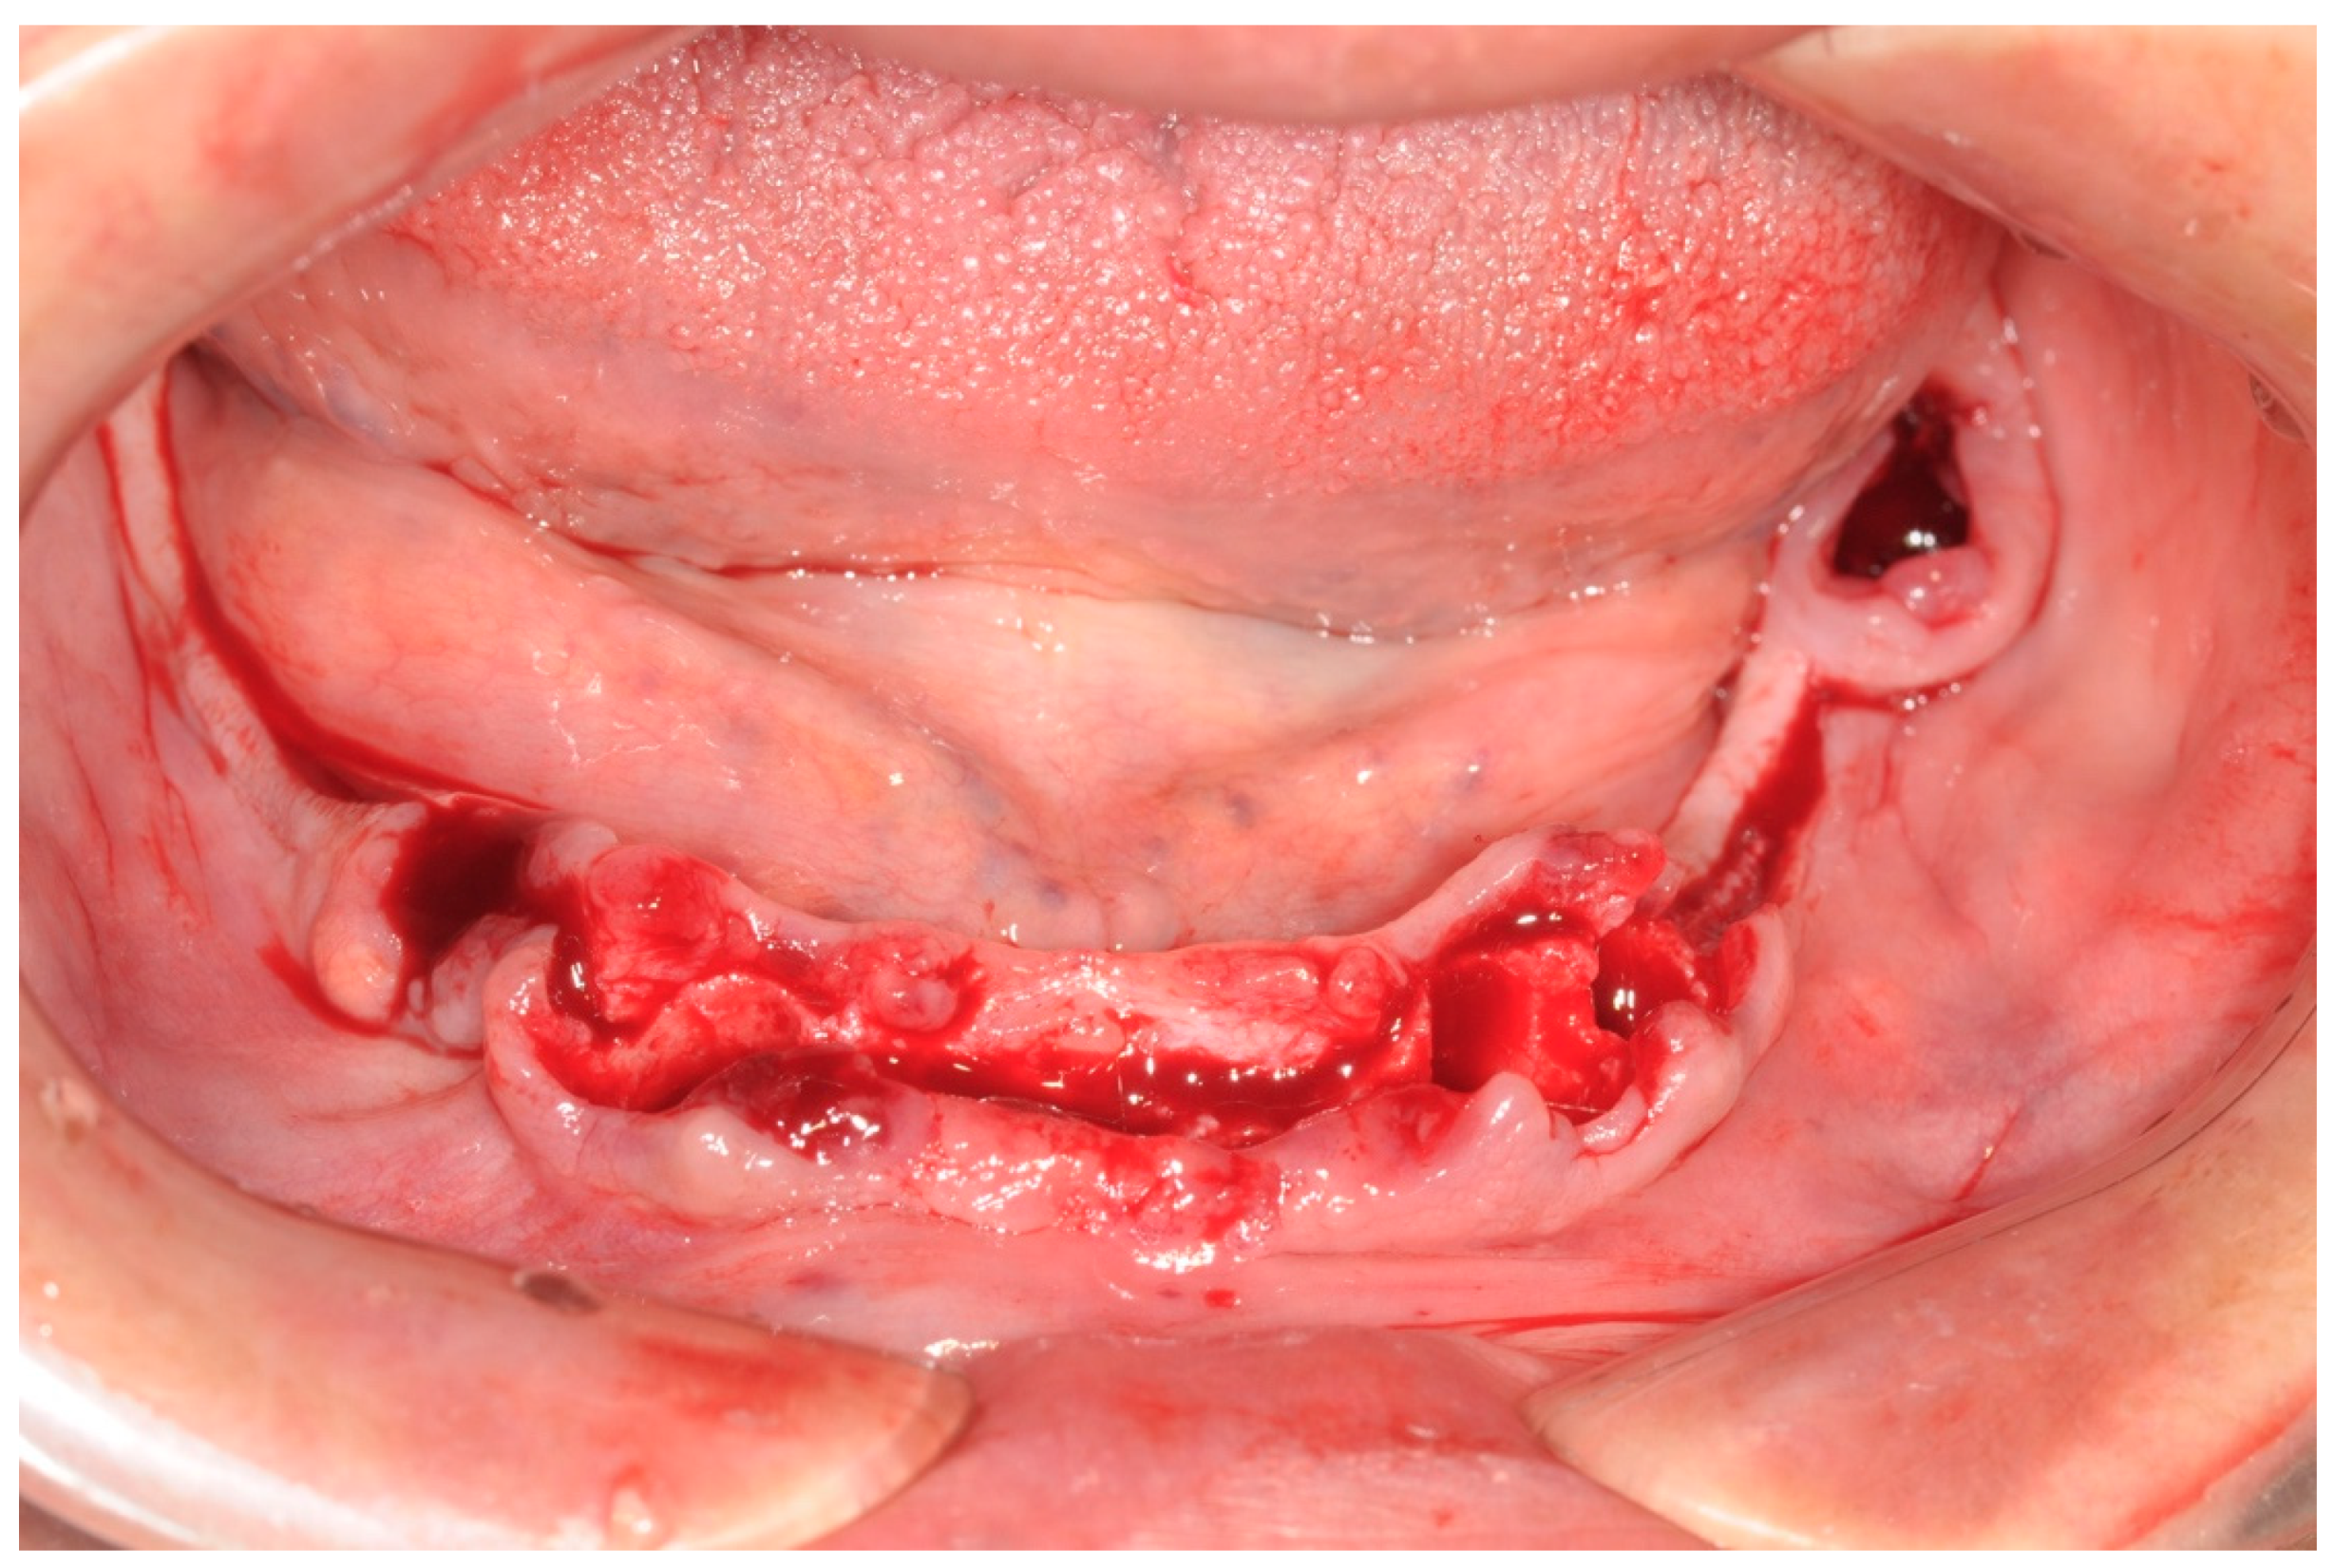

All patients enrolled in this study had panoramic radiographs and/or cone-beam computed tomography (CBCT) (Figure 1).

Figure 1. Preoperative panoramic X-ray.